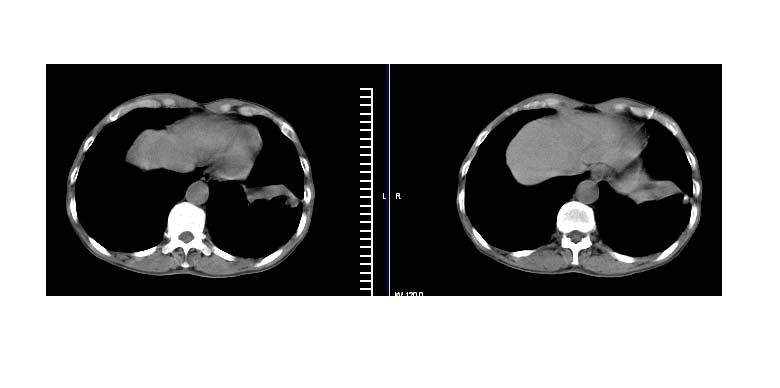

标题: CT11019:男性,66岁。发烧5-6天。治疗后无明显好转。 [打印本页]

标题: CT11019:男性,66岁。发烧5-6天。治疗后无明显好转。

阻塞性肺炎并不张,建议抗炎治疗后复查或增强

考虑左肺下叶炎症合并叶间裂积液,建议抗炎治疗后复查

左下肺实变,考虑炎症